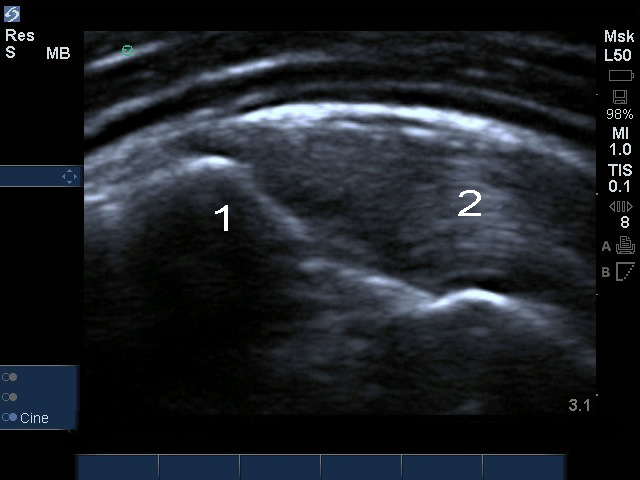

肩部缩放冈上肌止点缺损图像

肩部联合点内部撕裂 - 缩放

大结节 (GT)

冈上肌 (SS)